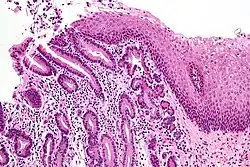

Micrograph of a gastro-esophageal junction with pancreatic acinar metaplasia. The esophageal mucosa (stratified squamous epithelium) is seen on the right. The gastric mucosa (simple columnar epithelium) is seen on the left. The metaplastic epithelium is at the junction (center of image) and has an intensely eosinophilic (bright pink) cytoplasm. H&E stain.